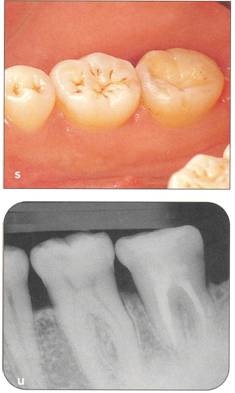

Fi 545e45f g 5-15 Three weeks after transplantation. Root canal therapy was started 2 weeks after transplantation. After temporary obturation with calcium hydroxide, the root canal was obturated with gutta percha in 5 weeks. Fi 545e45f g 5-1t Two and one half months after transplantation. |

Fi 545e45f g 5-1 u Definitive occlusal restoration of the donor tooth with composite resin. Fi 545e45f g 5-1v One year 3 months after transplantation. Normal periodontal ligament space and lamina dura are observed. |